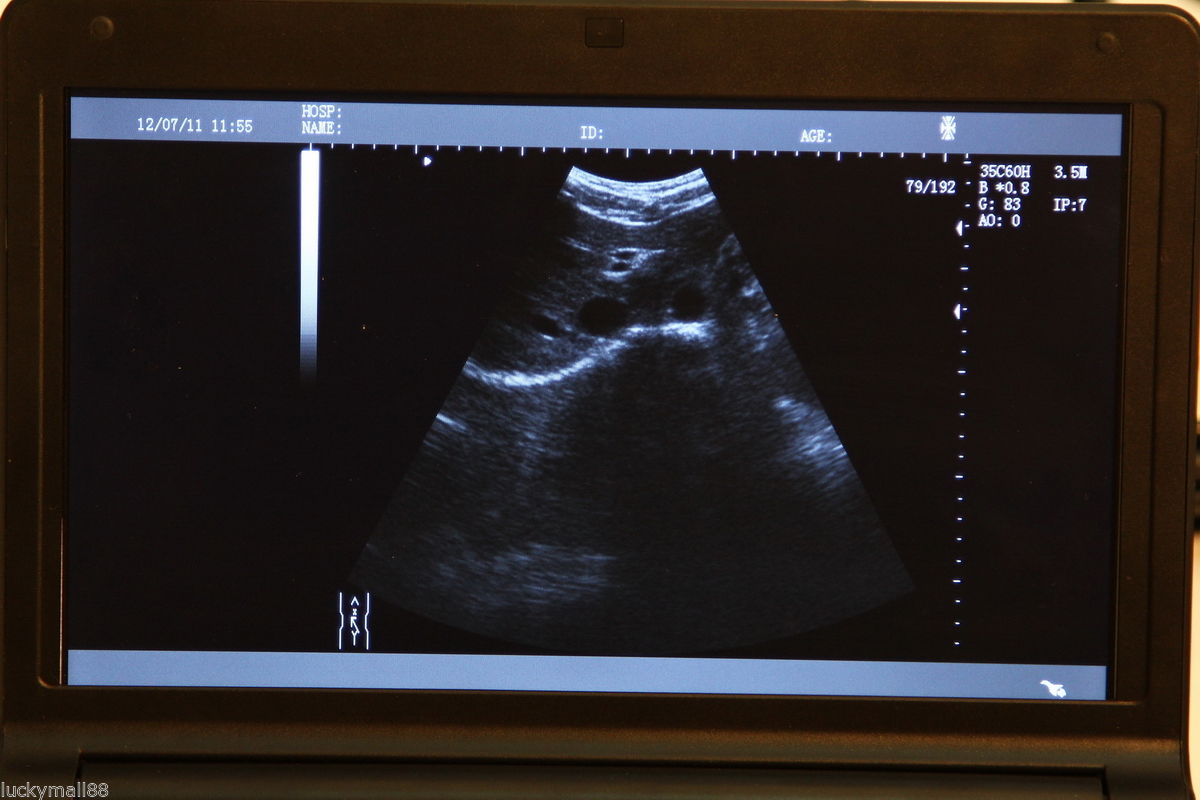

DIAGNOSTIC ULTRASOUND MACHINES FOR SALE

Laptop Ultrasound Machine, Notebook Digital Ultrasound scanner, 3.5 Convex probe

Sale price$ 1,648.00

Regular price$ 1,758.00